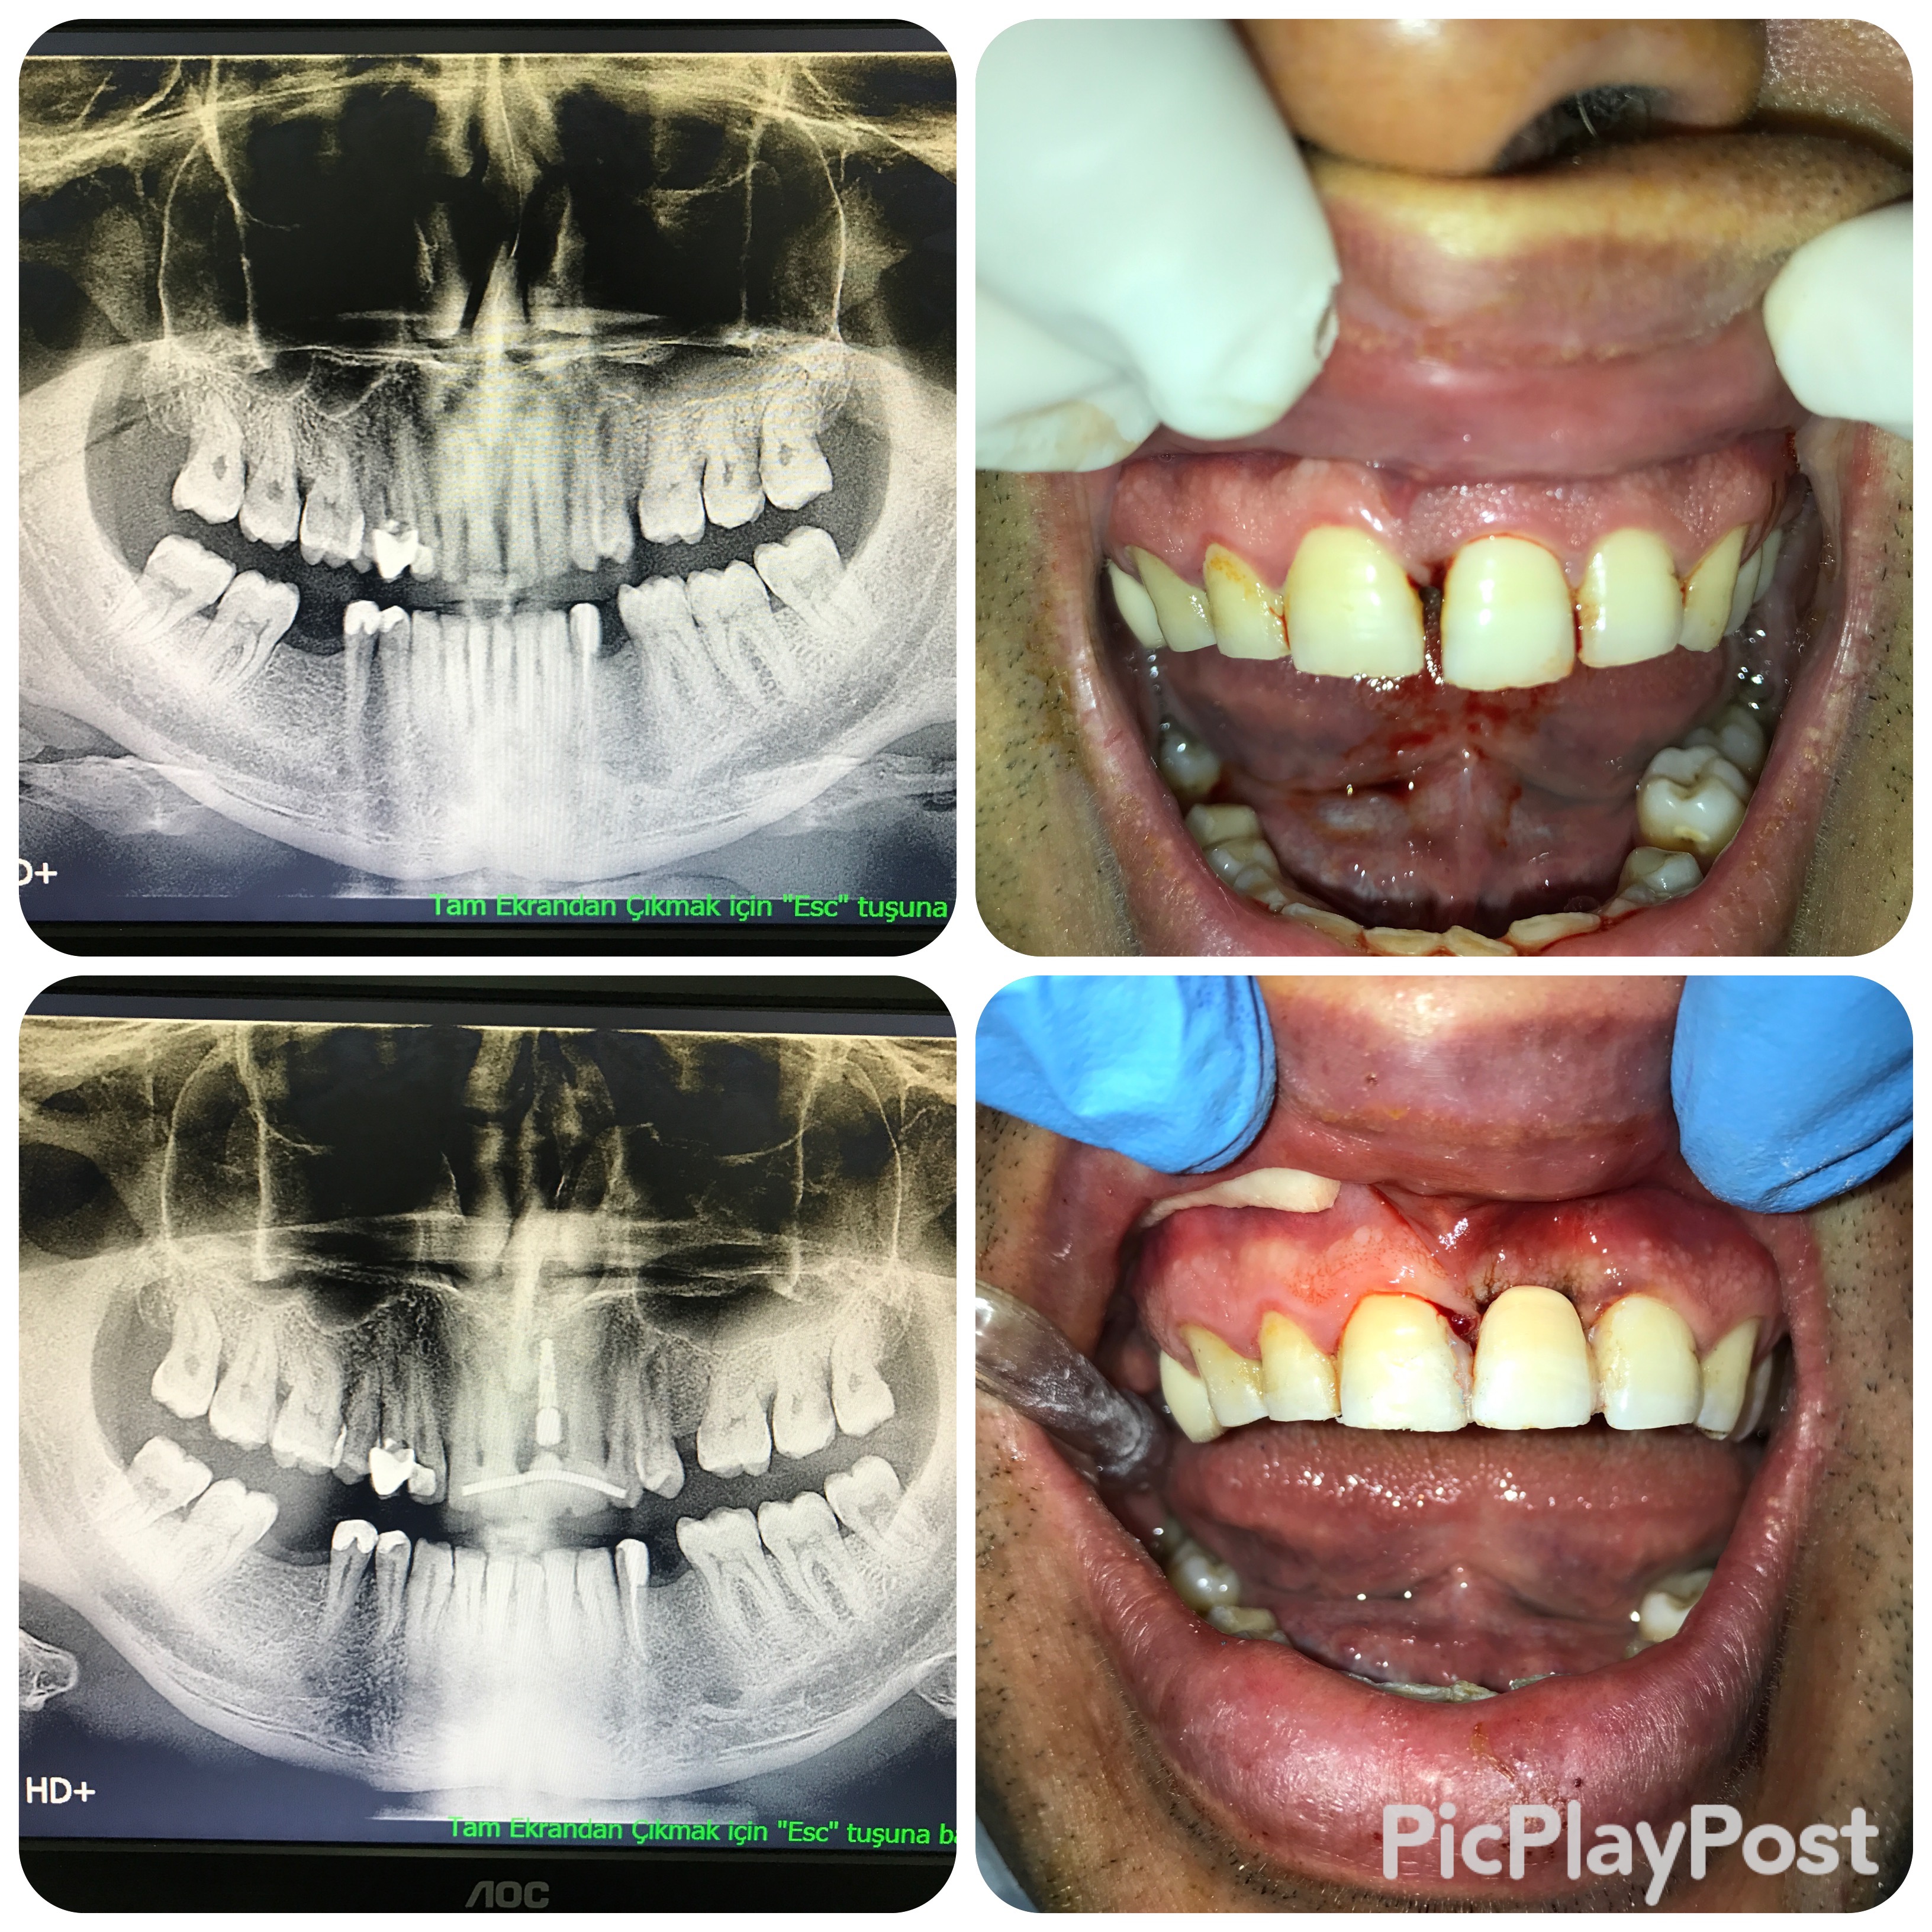

implant tedavisi